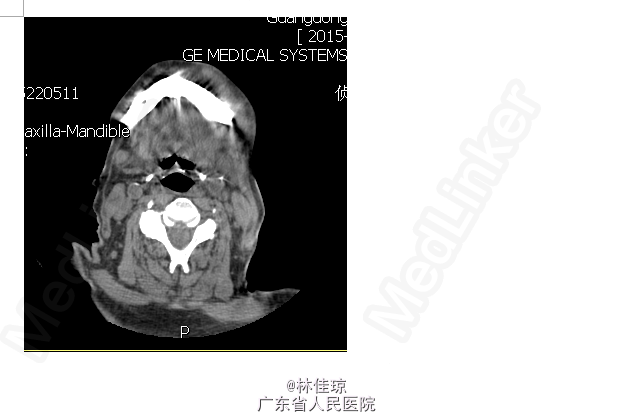

体查:头部不自主摆动,颈软,口腔异味,口腔未见明显出血点,可见少许血块。左下颌骨处可扪及4cm*1cm大小肿物,质硬,不可移动,局部皮温稍高,无触痛,表面未见分泌物。心肺腹查体未见明显异常。 行口腔科会诊,口腔科医师考虑左下后牙残根,牙龈红肿,探之易出血,建议予依信漱口。 大便常规:OB阴性, 血常规、PCT正常。 肿瘤指标正常; 凝血指标正常。 肾ECT:双肾总GFR 25.2ml/miin。 下颌骨CT未见明显异常,建议行下颌骨增强CT以排除局部感染或肿瘤; 下颌骨彩超:左下颌骨皮下软组织内实质性肿块,建议进一步检查。 胸片正侧位放射常规照片:慢支炎肺气肿。主动脉硬化。

1.下颌骨肿物查因:下颌骨炎症?下颌骨肿瘤?2.脑梗塞 该患者头部不自主摆动,无法配合行下颌骨X片,双肾总GFR 25.2ml/miin ,暂不考虑行CT增强检查。考虑炎症可能性大,暂予头孢+甲硝唑抗感染治疗及依信对症漱口治疗。

目前患者考虑下颌骨炎症,暂予头孢+甲硝唑抗感染治疗,但患者血常规、PCT正常,局部肿物质地硬,与下颌骨粘连,且不可移动,查肿瘤指标正常及CT未见肿物,该局部肿物是否有其他可能?